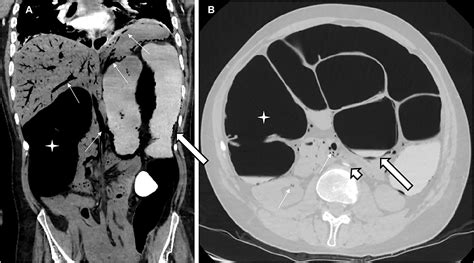

The gold standard for detecting portal venous gas is a CT scan of the abdomen, usually with intravenous contrast. On a scan, gas appears as low-attenuation, branching, linear lucencies that extend into the periphery of the liver. This pattern is distinct from pneumobilia (gas in the bile ducts), which typically resides in the central portion of the liver and follows the path of the biliary tree.

Distribution Extends to the liver periphery Central, follows biliary tree

Morphology Branching, thin lucencies More rounded, central